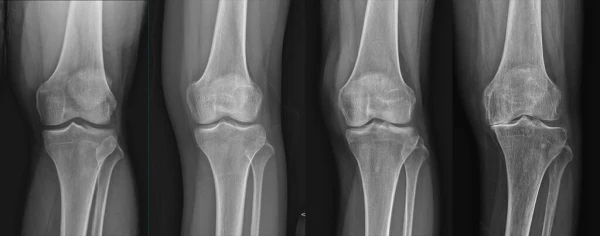

통풍을 적절히 치료하지 않을 경우, 발작성 관절염의 빈도가 증가하고 침범하는 관절 수도 더 많아지며, 회복에 필요한 시간도 증가합니다. 반복적인 관절염은 관절을 점차 손상시키며, 만성적인 관절염으로 진행될 수 있습니다. 또한 통풍성 결절이라 불리는 덩어리가 관절 주위나 피부 조직에 나타날 수 있습니다. 이러한 결절은 요산 결정체의 덩어리로 어느 부분에서든 형성될 수 있으며, 주로 팔꿈치, 귀, 손가락, 발가락, 발목 등에서 발생할 수 있습니다. 때로는 요로 결석을 형성하기도 합니다.

1) 한 군데 관절(엄지발가락, 발목, 무릎 등)이 갑자기 붓고 빨갛게 변하며, 손을 움켜쥘 수 없을 정도로 심한 통증이 발생합니다.

4) 엄지발가락 관절에 염증이 잘 발생하는 것이 특징이며, 무릎, 발, 발목, 손목, 팔꿈치 등 다른 관절에서도 발생할 수 있습니다.